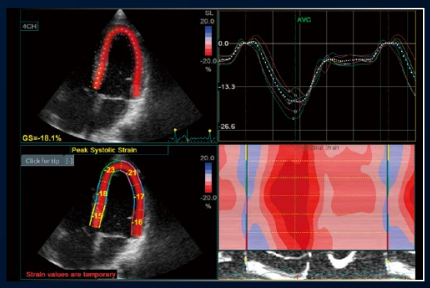

AFI

心尖部画像を基に心筋のスペックルをトラッキング。

局所心筋壁運動の程度とタイミングを

簡単に評価できます。